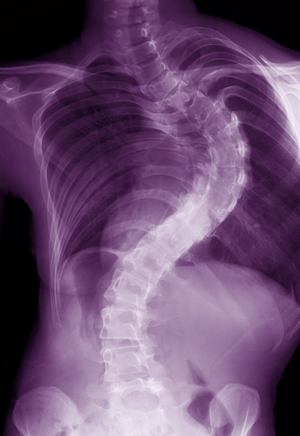

X-ray image of a child with AIS Figure 1: Spinal x-ray of a child with AIS. © 2013 Ikuyo Kou, RIKEN Center for Integrative Medical Sciences

Adolescent idiopathic scoliosis (AIS) is the most common pediatric skeletal disease, causing complex rotational deformity of the spine in approximately 2% of school-age children worldwide. Recent studies have implied that AIS may, at least in part, be caused by genetics, but the pathogenesis of AIS still remains poorly understood. An international research team led by Shiro Ikegawa from the Laboratory for Bone and Joint Diseases at the RIKEN Center for Integrative Medical Sciences has now identified another gene that may contribute to AIS by altering spinal development1.